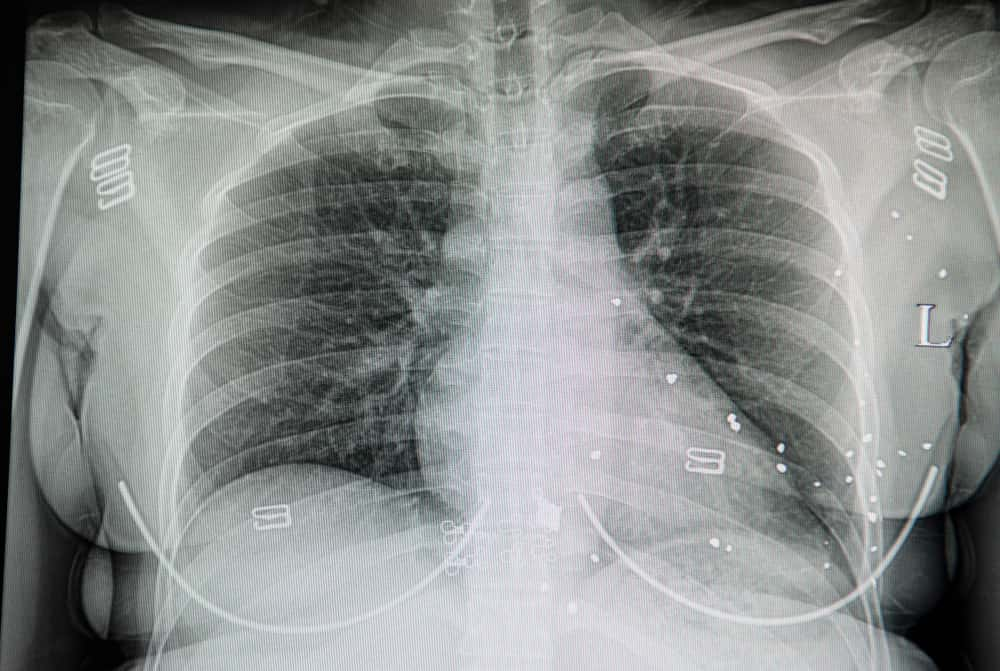

It was like something out of a horror scene and I think I was in shock because I felt so weird and out of place afterward. Later on, I found out that upon a closer inspection of the X-rays, the poor (and very large) man's sternum had given way. The going theories were either that his sternum had broken when his chest hit the steering wheel during his accident or from the CPR performed by the paramedics. People don’t realize how dangerous CPR can be.

The bone had splintered and punctured into his major blood vessels so we had just been pumping blood into his pericardium (heart sac). That’s what exploded when the OR team cut him open. There was little we could do to save this man's life. After that episode, the sight of blood never bothered me anymore.